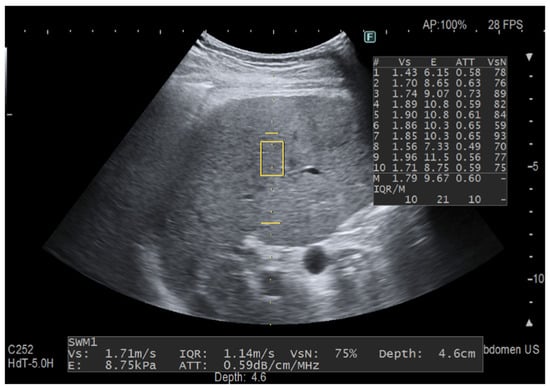

Figure 1.

Fat quantification with the previous ATT algorithm. The yellow rectangle is the region of interest (ROI) for stiffness measurement and the yellow horizontal line indicates the depth of the ATT measurement area in the far field, which is set at 100 mm. The ATT measurement area has a fixed size and the measurement of the attenuation coefficient is given in dB/cm/MHz together with liver stiffness measurement, which is shown both in m/s and kPa. ATT quantifies liver fat content in an areathat has a length of 6 cm and is set at 40–100 mm from the skin. This measurement was taken in a 64-year-old patient with chronic hepatitis C following the protocol for liver stiffness measurement and with a VsN always ≥50%. The attenuation coefficient value is within the normal range.